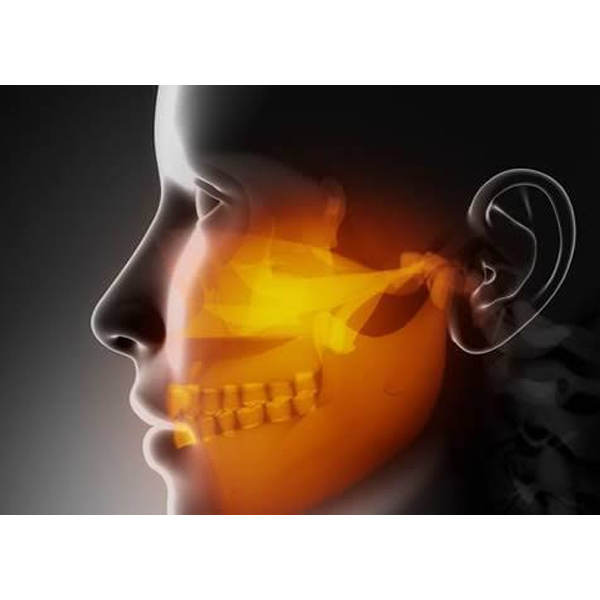

To correct a disease, injury or defect of your face, jaw or mouth including : Wisdom Tooth Removal, Facial Deformity, Oral Cancer, Facial Trauma